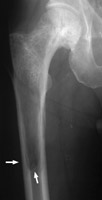

Diagnosis:Paget's Disease Discussion:Paget's disease has three distinct phases visible radiographically: a lytic phase, a sclerotic phase, and a mixed lytic-sclerotic phase. When involvement of the lytic phase is present in a long bone, the lytic changes may advance as a V- or wedge-shaped radiolucent area, clearly demarcated from the adjacent bone. This has been likened to a blade of grass. References: